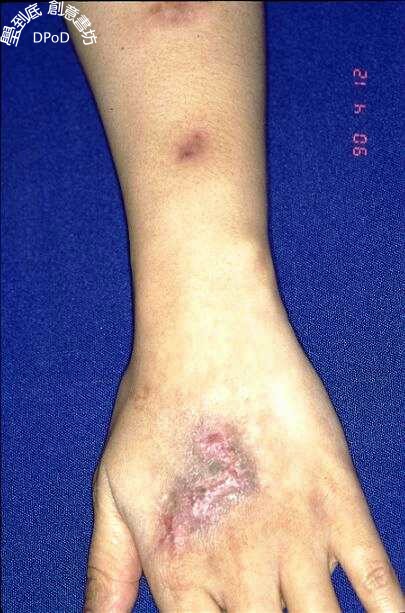

孢子絲菌樣皮膚分枝桿菌感染

Sporotrichoid mycobacterial infection of the skin

沿著線狀排列的進行性皮膚病灶,考慮最常見的是孢子絲菌症,其次是分枝桿菌或奴卡式菌的感染。 分枝桿菌的感染常要3個月到半年的療程。

診斷重點--手腳外傷後,漸進上行性的不痛不癢線狀排列結節,治療很久無效者。

25歲女性主訴左手臂不痛不癢的多發病灶兩年之久

治癒後通常會留下疤痕。